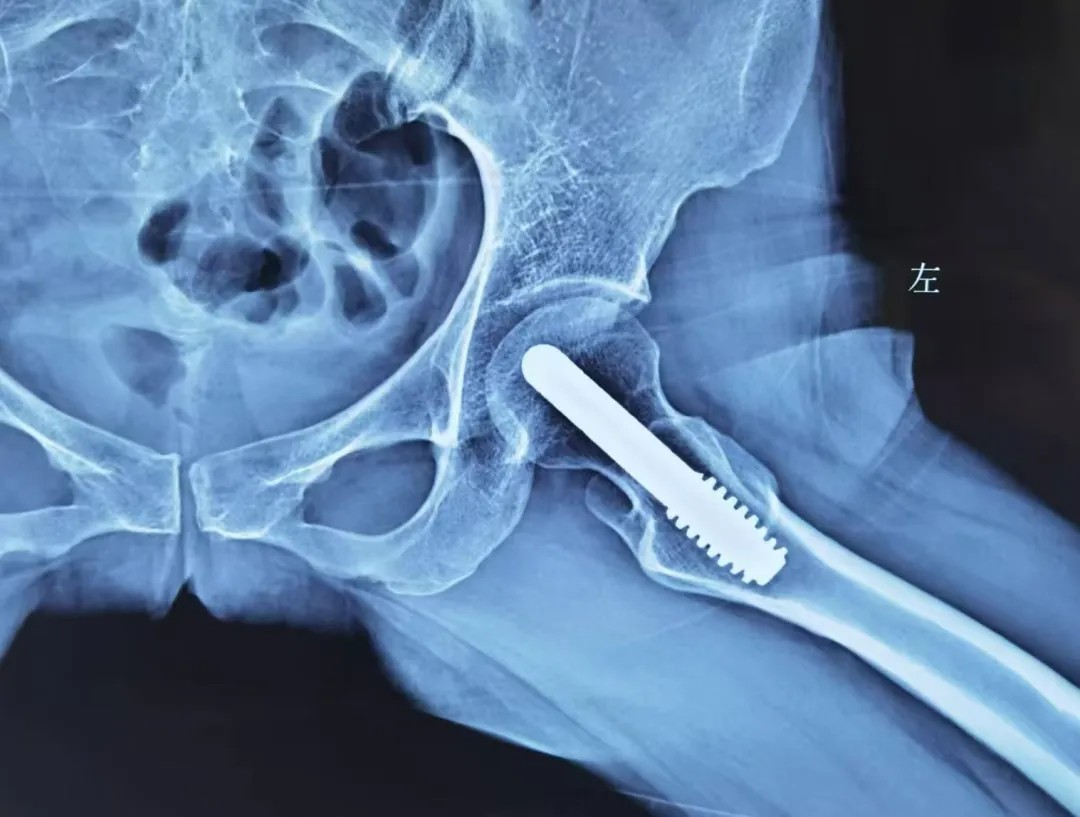

晚期:換髋昰(shi) “最優(you)解”

股骨頭壞死晚期,此時股骨頭完全塌陷,保留股骨頭也(ye)沒有(yǒu)意義了(le)。此時多(duo)采取人(ren)工(gong)髋關節(jie)置換術(shù),能(néng)快速(su)緩解疼痛、恢複活動(dòng)能(néng)力(li),目(mu)前(qian)手術(shù)技(ji)術(shù)成(cheng)熟,假體(ti)壽命可(kě)達20年(nian)左右。